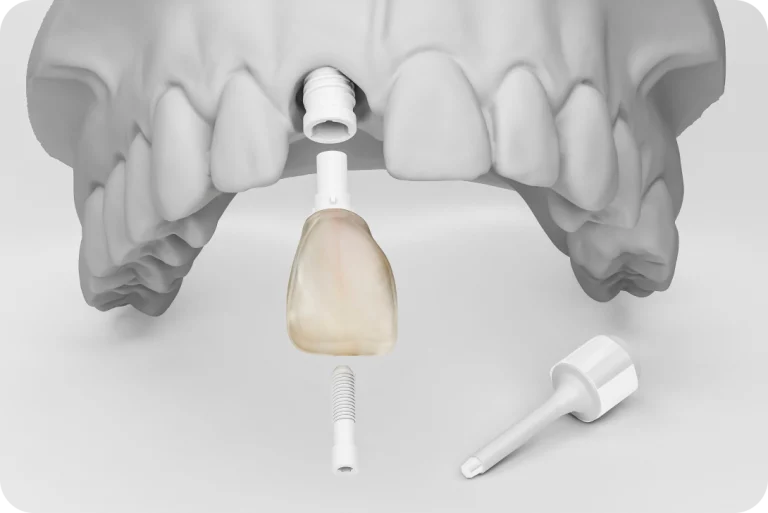

L’implantologie permet de replacer une dent en cas de maladies dégénératives, d’infections, de traumatismes ou autres. Un dispositif, appelé l’implant, permet de remplacer la racine de la dent manquante. Une couronne sera alors placée sur cet implant pour remplacer la partie extérieure de la dent. Notre dentiste à Toulouse peut traiter les cas avancés nécessitant une ou plusieurs extractions bucco-dentaires et vous permettre de retrouver l’intégrité de votre denture après une carie ou un choc.